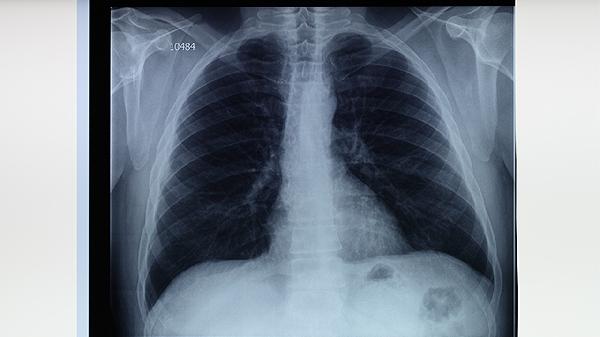

早期规范治疗是治愈的关键。确诊后应立即采用异烟肼片、利福平胶囊、吡嗪酰胺片、乙胺丁醇片等药物联合治疗,强化期需持续2-3个月,巩固期需持续4-6个月。治疗期间需定期复查胸部影像学和痰结核菌检查,评估治疗效果。多数患者经全程规律用药后,肺部病灶可完全吸收,痰菌转阴,达到临床治愈标准。治疗过程中需注意药物不良反应监测,常见肝功能损害可通过护肝药物如谷胱甘肽片辅助治疗。